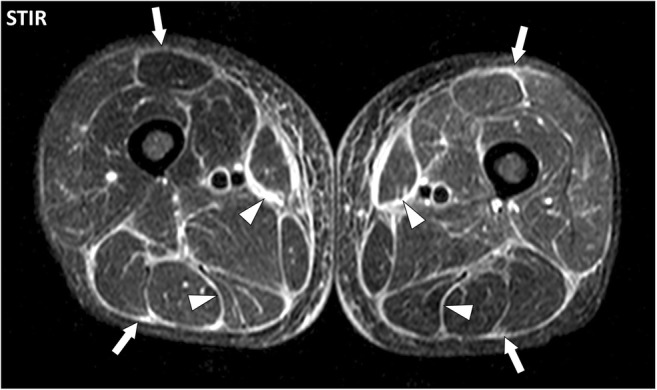

Fig. 10.

Axial STIR image of the thighs of a 50-year-old male with eosinophilic fasciitis. MRI demonstrates bilateral symmetrical diffuse involvement of the deep peripheral fasciae (arrows) and deep intermuscular fasciae (arrowheads), which are thickened with high signal intensity. The fascia superficialis is barely involved and the signal of the muscles is normal